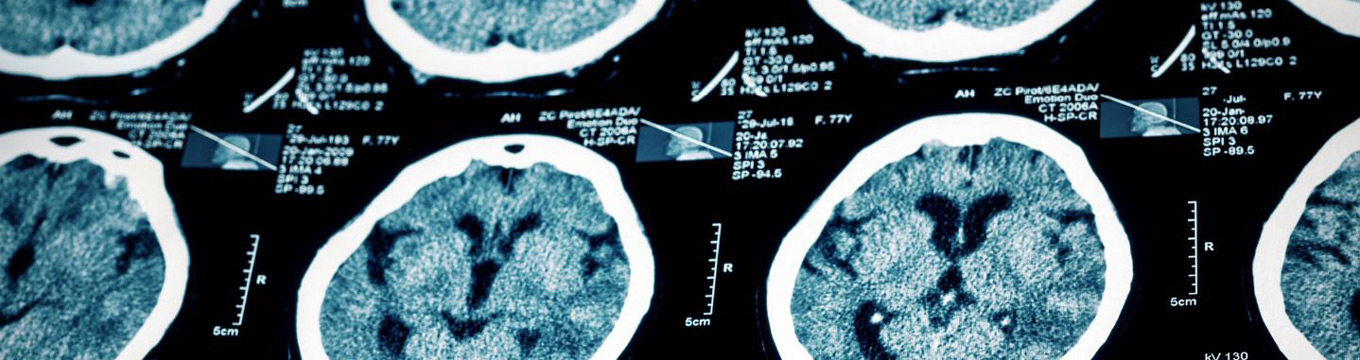

You know how our nervous system transmits nerve impulses between different parts of the body. We treat you with much care and endearment treating disorders that affect the brain, spinal cord, and nerves.

• Stroke